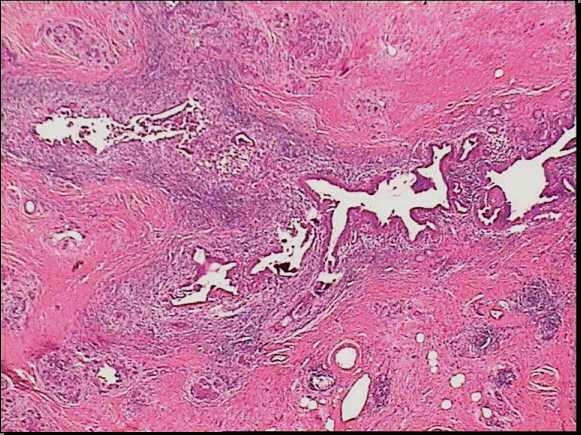

Low-power view of a autoimmune pancreatitis showing a periductular inflammatory cells. The remainder of pancreatic tissue is fibrotic with complete acinar atrophy.

High-power view of the same slide shows the heavy inflammatory infiltrate in the epithelium layer with erosion and duct distorsion.